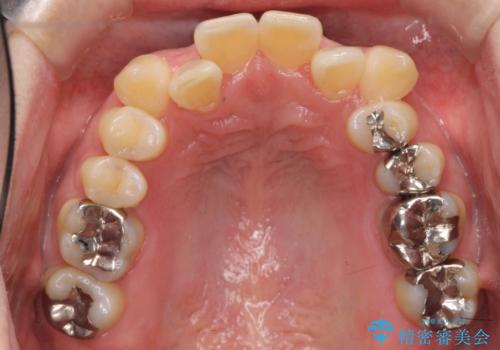

40代の矯正 八重歯を綺麗に

上の前歯が内側に入っているクロスバイトは、笑った時に影になってしまい、かなり目立ちます。

内側に入っている前歯を外に出すだけで劇的に印象が変わります。